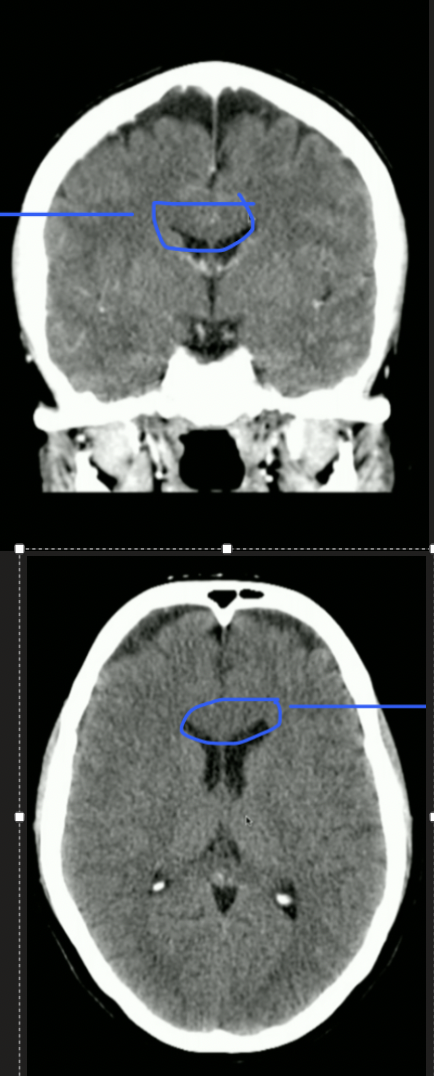

<p>What is highlighted?</p>

What is highlighted?

• 3rd Ventricle

• CSF then goes to Cerebral Aqueduct

<p>What is Top + Bottom Circle + Arrow?</p>

What is Top + Bottom Circle + Arrow?

• Top: 3rd Ventricle

• Bottom: 4th Ventricle

• Arrow: Cerebral Aqueduct